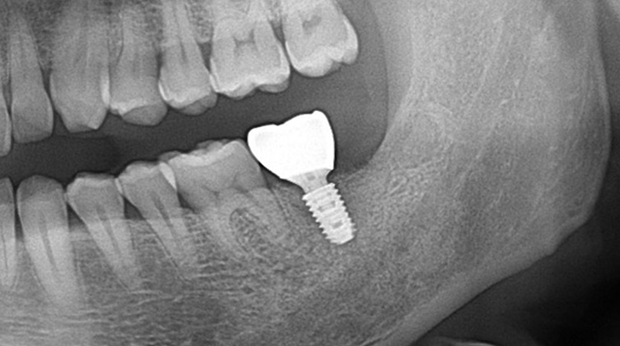

의식하진정법(수면마취)/임플란트

고난도 수술 진료

임플란트와 사랑니 발치는 외과적 시술로 잇몸을 절개하는 외과적 시술은

짧으면 짧을 수록 시술 후 붓기와 통증이 최소화됩니다.

치과의사 경력 14년차 구강외과 전문의가 빠르고 안전하게, 아프지 않게 수술해 드립니다.

치과경력 14년차 구강외과 전문의

연세대학교 치과대학 구강외과 임상 조교수